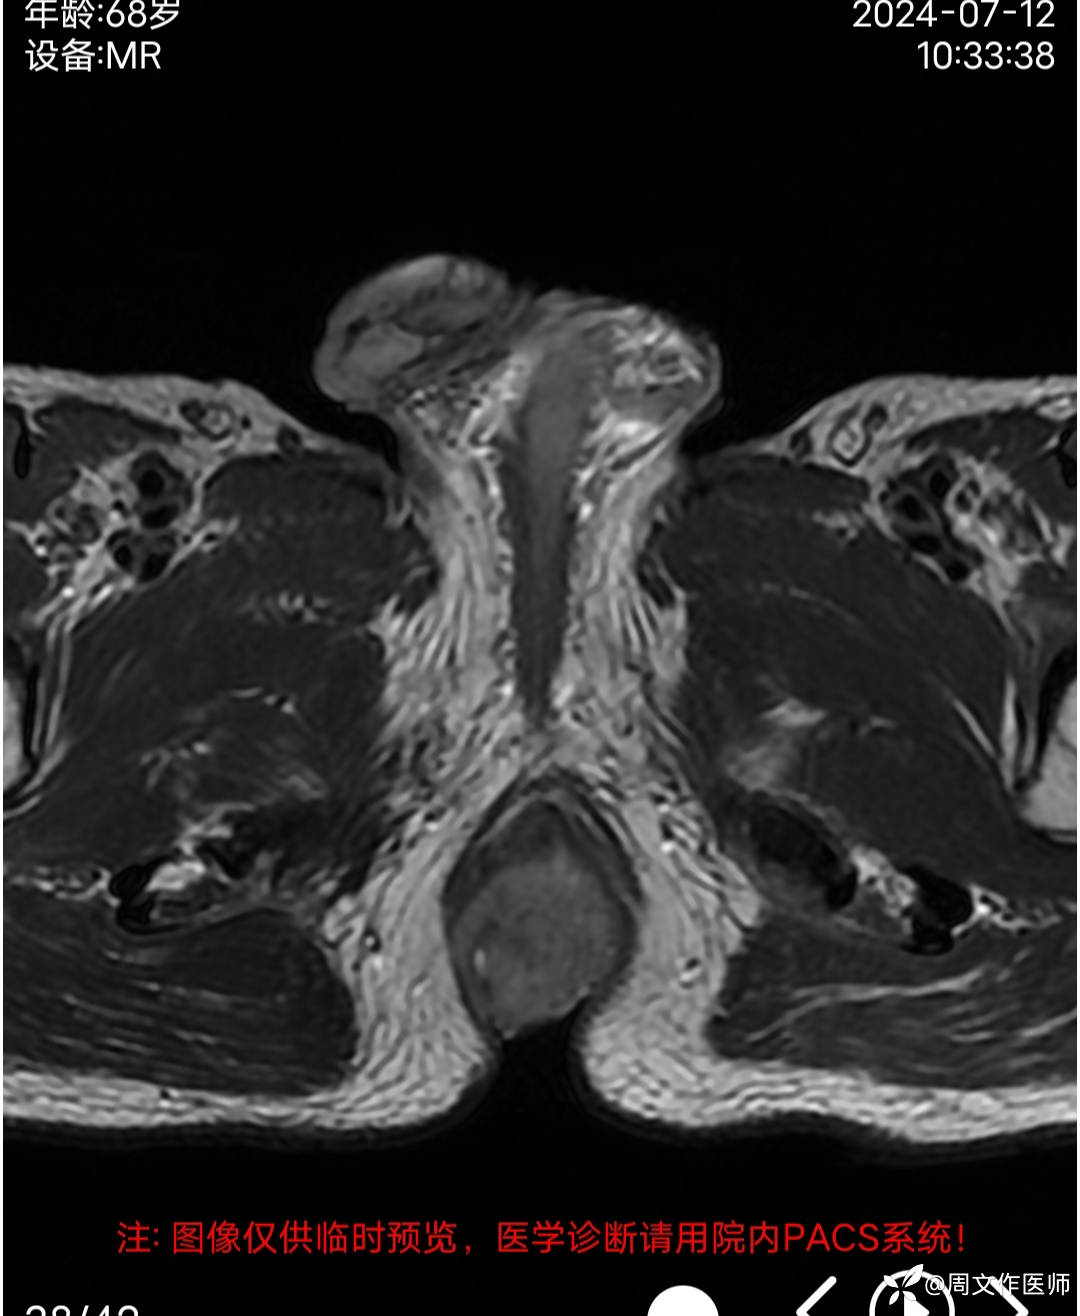

MRI检查